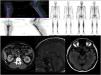

Figure 1.Radiological findings: Characteristic bone involvement on PET/CT and bone scintigraphy, CT of the abdomen with no pathological findings in the kidney; MRI of the brain. Sagittal slices in T1 and axial slices enhanced in T2 FLAIR. The sellar region shows no significant pathological abnormalities. Multiple hyperintense signal abnormalities are identified on T2 FLAIR in the brain stem, especially in the area of the pons.

Computed tomography (CT) of the chest, abdomen and pelvis: lung parenchyma featuring a ground-glass pattern with interstitial thickening in the right lower lobe consistent with an inflammatory process, without any other findings of note.

Magnetic resonance imaging (MRI) of the brain: multiple small signal abnormalities on both sides of the midline of the brain stem and cerebellum. No pathological abnormalities were seen in the pituitary gland.

Positron emission tomography/computed tomography (PET/CT): diffuse involvement of bone marrow of long bones, with greater uptake in the left proximal tibial metaphysis. Hypermetabolic focus in left pons in relation to active lesion. Increases in hypermetabolic density in right lung consistent with inflammatory signs which, along with the hypermetabolic lymphadenopathy reported in the right paratracheal and subcarinal region, were suggestive of an inflammatory process.